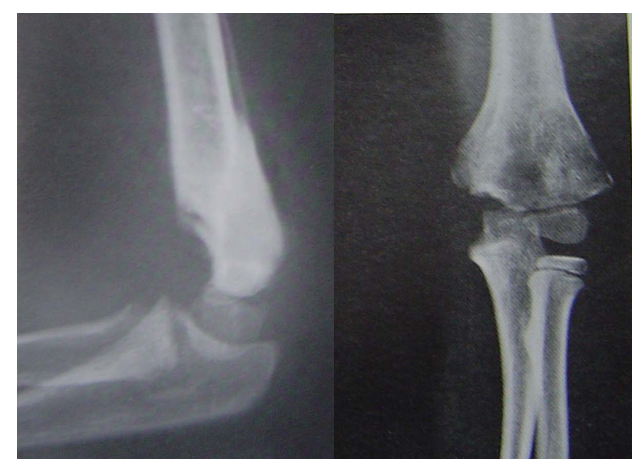

屈曲型伸直复位,伸直固定是方法之一。但石膏容易滑脱另一方法,伸直复位后屈曲肘关节,向后推挤维持复位,然后经皮克氏针固定。A、B术前x线片C 、D 手法复位 E 克氏针固定后